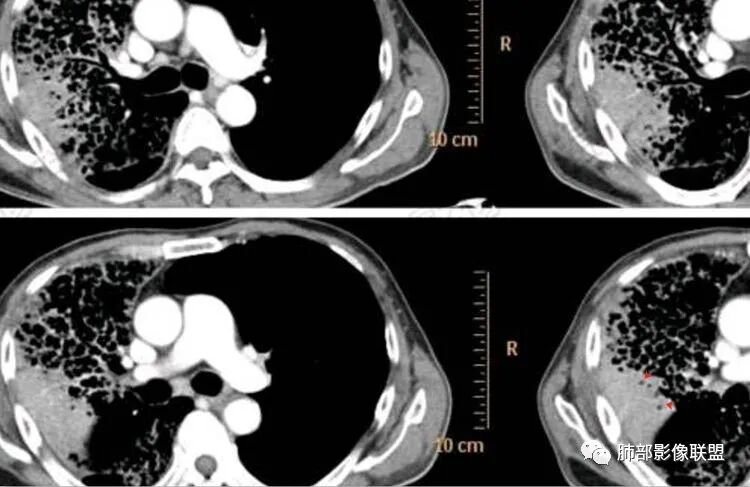

1.老年男性,咳大量白色泡沫痰,6个月长病程。白细胞轻度增高,CYFRA211增高。

2.影像显示右肺较广泛蜂窝样阴影,上肺及下肺为主,未见液平及重力分布趋势。其中上叶后段及下叶后基底段近胸膜下可见实性密度区,实性密度区强化明显,周边特征掩盖不清。

3.病灶区叶段支气管显示较满意,未见明显狭窄、阻塞或截断。

4.左肺偶见小结节,但未见典型播散结节影。注意左肺未见蜂窝影。

5.纵隔轻度右移,提示右肺体积整体轻度减小。

6.纵隔未见增大淋巴结。右肺门掩盖。